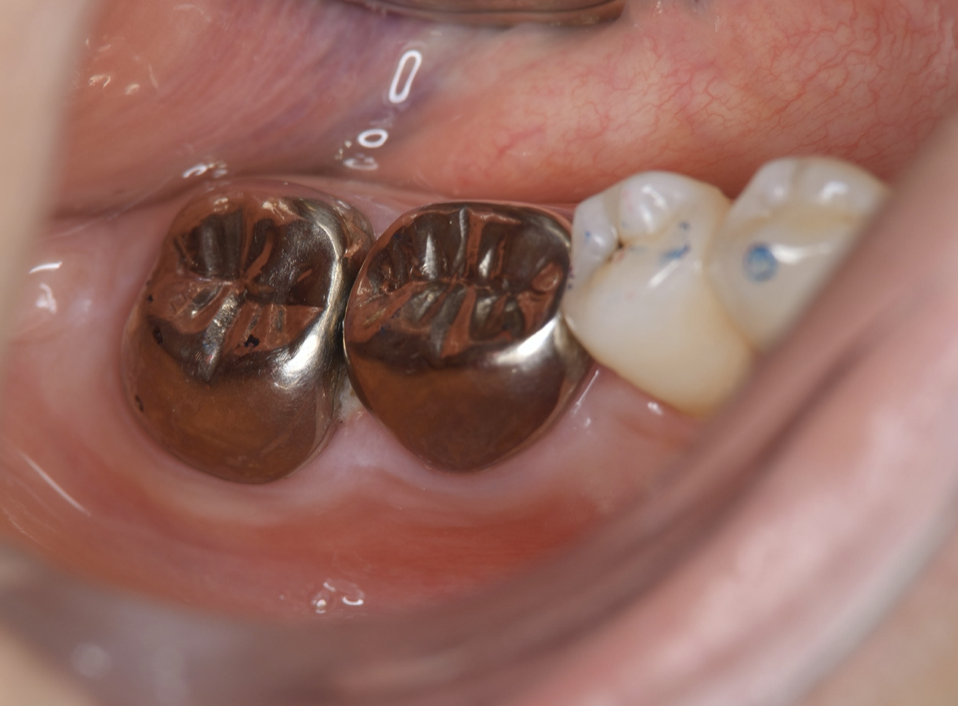

Endodontic treatment was initiated at 14 days after transplantation (8, 17). Root canal treatment for #48 was performed using Ni-Ti files (Pro Taper Next, Dentsply Sirona, Tokyo, Japan) to accommodate the complex morphology of the root canal and for minimal removal of the tooth structure during formation of the access cavity. Root canals were medicated with calcium hydroxide paste and then filled with gutta percha. The splint was also removed four weeks after the operation and a resin core was used as an abutment construction. In an attempt to appropriately modify contact and the crown morphology, a crown prosthesis was made with a full metal crown, with occlusal contact confirmed with use of a temporary crown and easy to visualize markings on occlusal paper. The full metal crown was cemented six months later (Figure 7).

Bone regeneration was confirmed before and after grafting, after root filling, and after placement of the prosthesis, based on X-ray imaging results (Figure 8). There was no pathologic mobility or pain during mastication, and the tooth showed good function. The patient was very satisfied with the treatment results (Figure 9).

Figure 7.Inter-oral photo obtained after treatment. Full metal crowns were inserted for #46, #47. Pathological mobility and bleeding on probing were not seen, and the transplanted tooth showed good function.